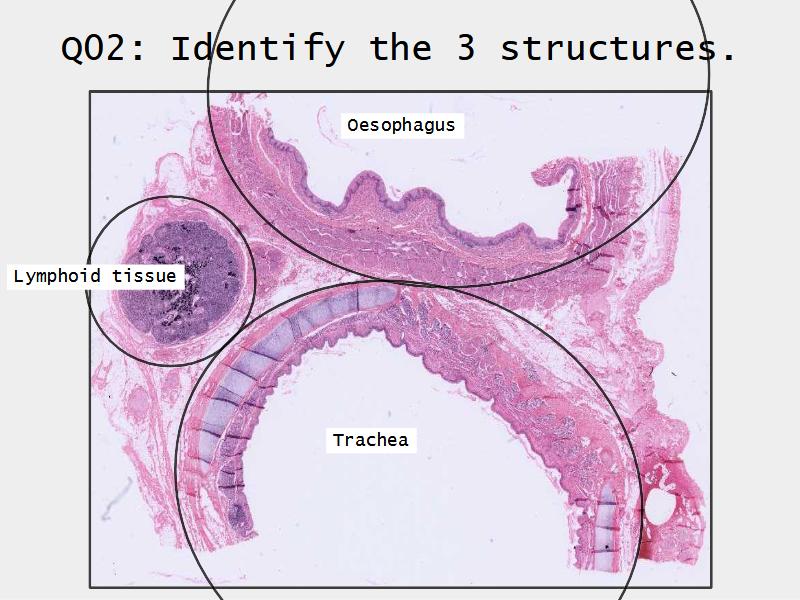

Slides: Respiratory System

- Slide 73: Trachea

Trachea